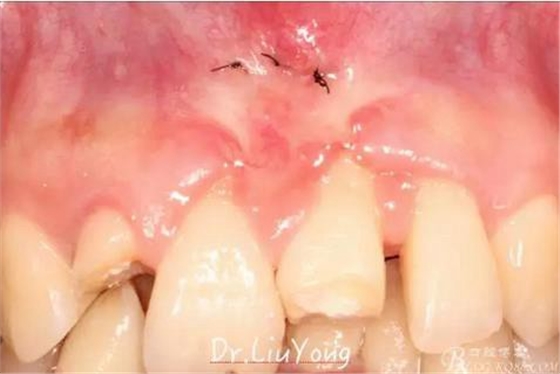

上唇系帶手術后一周拆線,如上圖